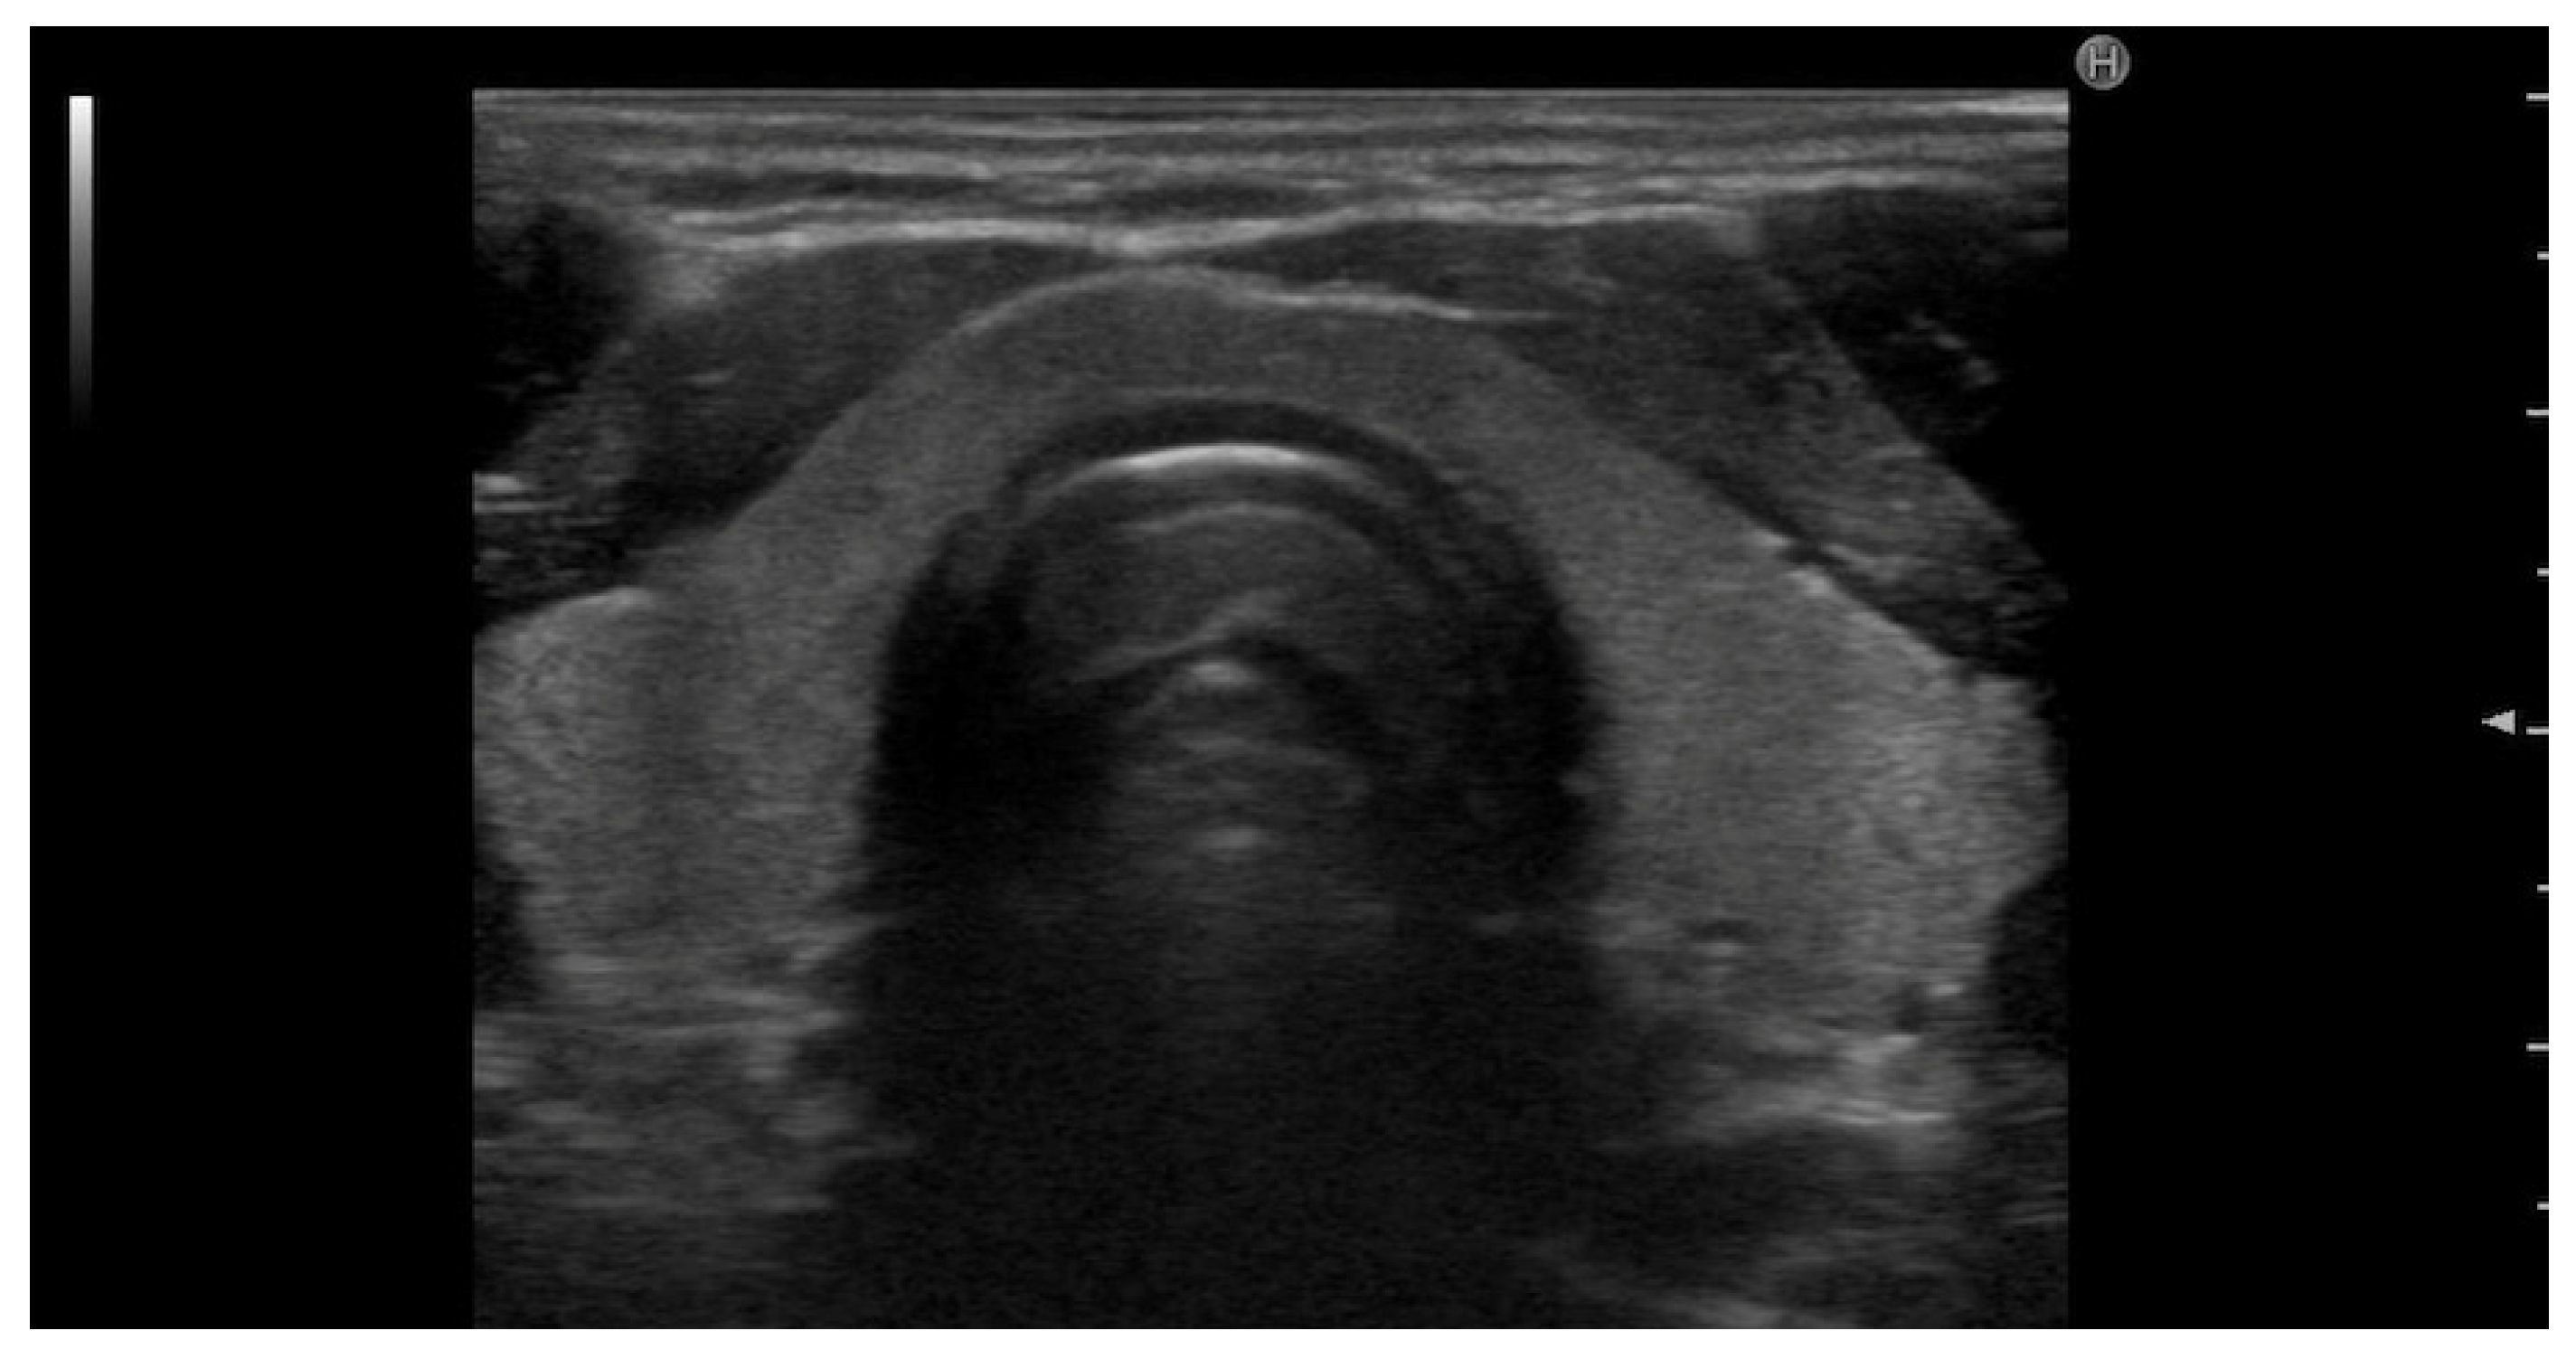

Figure 1.

Transverse ultrasound image of the neck showing the anatomical structures of the thyroid region. The image highlights the right and left lobes of the thyroid gland, the isthmus (Is), and central trachea. Also labeled are the sternocleidomastoid muscle (SCM), carotid artery (C), and jugular vein (JV), serving as key anatomical landmarks for orientation during thyroid ultrasound examination.